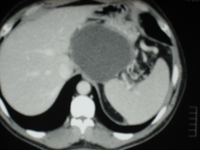

Carcinome hepato cellulaire